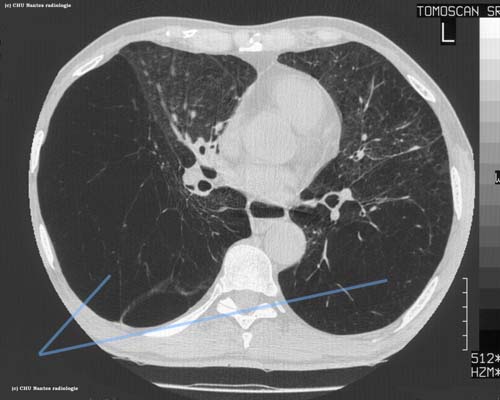

Emphysème pulmonaire sévère

coupe TDM en fenêtre parenchymateuse

emphysème sévère avec quasi-destruction du parenchyme pulmonaire ( aspect dit de poumon évanescent )